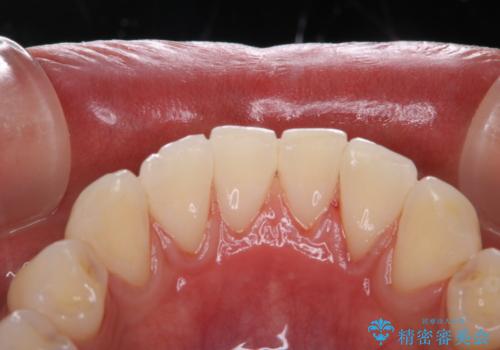

PMTCでは専門的な機械や材料を使用して、徹底的に汚れを除去するため、虫歯・歯周病・口臭予防などにつながります。

PMTCを行うことで、ご自身本来の歯の色になり自然な明るさになります。

口元が自然な明るさになることで、より清潔感のある印象になるため結婚式・行事やイベント前などにもPMTCを行うはおすすめです。

また、ホワイトニングを考えている場合も、まずはPMTCで汚れの除去を行って判断することをおすすめします。